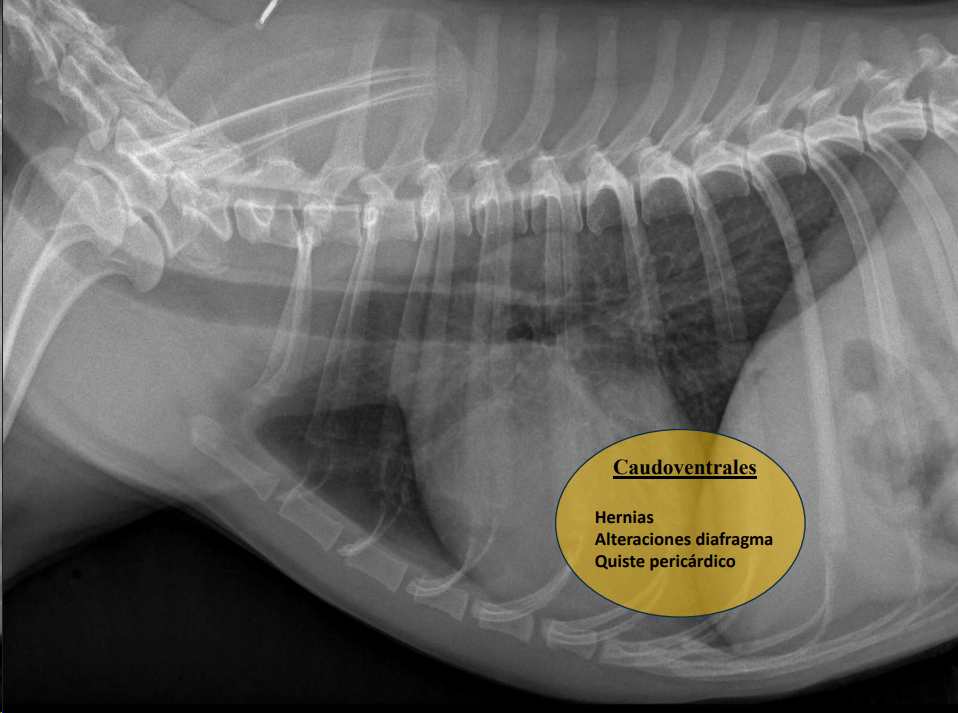

- Masas mediastínicas (craneodorsales, hilares, caudodorsales, caudoventrales, craneoventrales).

Caudodorsales: hernia paraesofágica, tumores neurogénicos, granulomas.

Craneoventrales: linfoma, timoma, tumor tiroideo, histiocitosis, lipoma, fibrosarcoma, linfoadenopatía esternal o craneal, absceso, aneurisma auricular.